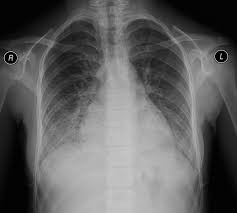

Начало острое с высокой лихорадкой, кровохарканьем или легочным кровотечением, одышкой. При аускультации обилие звонких влажных хрипов в средних и нижних отделах легких, рентгенологически - множественные очаговые или сливные затемнения в обоих легочных полях. Тяжелый, прогрессирующий гломерулонефрит развивается почти одновременно, быстро приводя к почечной недостаточности. Повторные кровохарканье и гематурия ведут, как правило, к анемии, усугубляющейся при почечной недостаточности. При лабораторном исследовании: анемия, лейкоцитами и повышенная СОЭ. Характерным иммунологическим признаком болезни являются антитела к базальным мембранам почки. Прогноз обычно неблагоприятен - смерть наступает в ближайшие 6 мес - 1 год от начала болезни при явлениях легочно-сердечной или почечной недостаточности.

- Инструментальная диагностика. При подозрении на синдром Гудпасчера выполняется рентгенография легких спирометрия, УЗИ почек, ЭКГ, ЭхоКГ.

При проведении диагностических мероприятий врачам необходимо исключить такие заболевания как рак легких, бронхоэктазии, туберкулез, гемосидероз легких, системную красную волчанку, геморрагический васкулит, синдром Черджа-Стросс, микроскопический полиангиит, криоглобулинемию и другие.